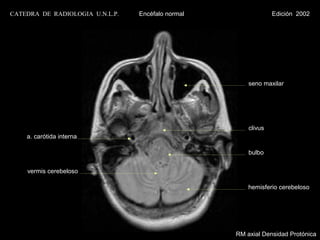

seno maxilar

clivus

a. carótida interna

bulbo

vermis cerebeloso

hemisferio cerebeloso

RM axial Densidad Protónica